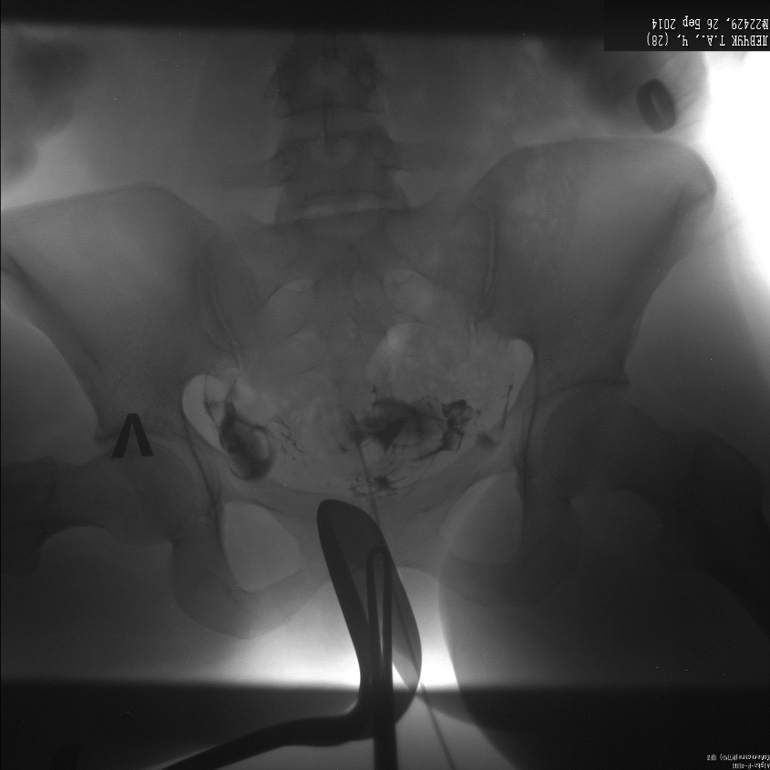

Метросальпингография, посмотрите, неужели все так плохо?

заключения нет, просто сказали, что правая проходима, а левая нет, и трубы тонкие, длинные и закрученные, на лапару отправляют!